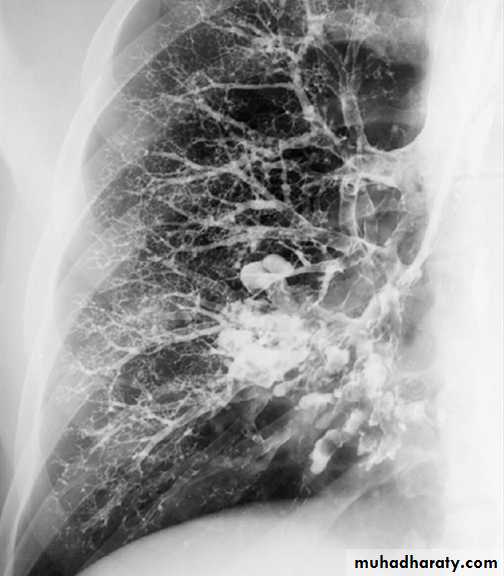

bronchiectasis